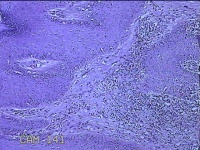

性别

男

年龄

45岁

临床诊断

皮下结节

一般病史

发现左侧一结节,伴局部瘙痒不适1年。

标本名称

左侧结节

大体所见

灰白暗红色带皮肤样结节0.8x0.7x0.3cm一个,表面糜烂,切开结节呈实性,切面灰白粉红色,质软。

图2

感觉像表皮样囊肿?